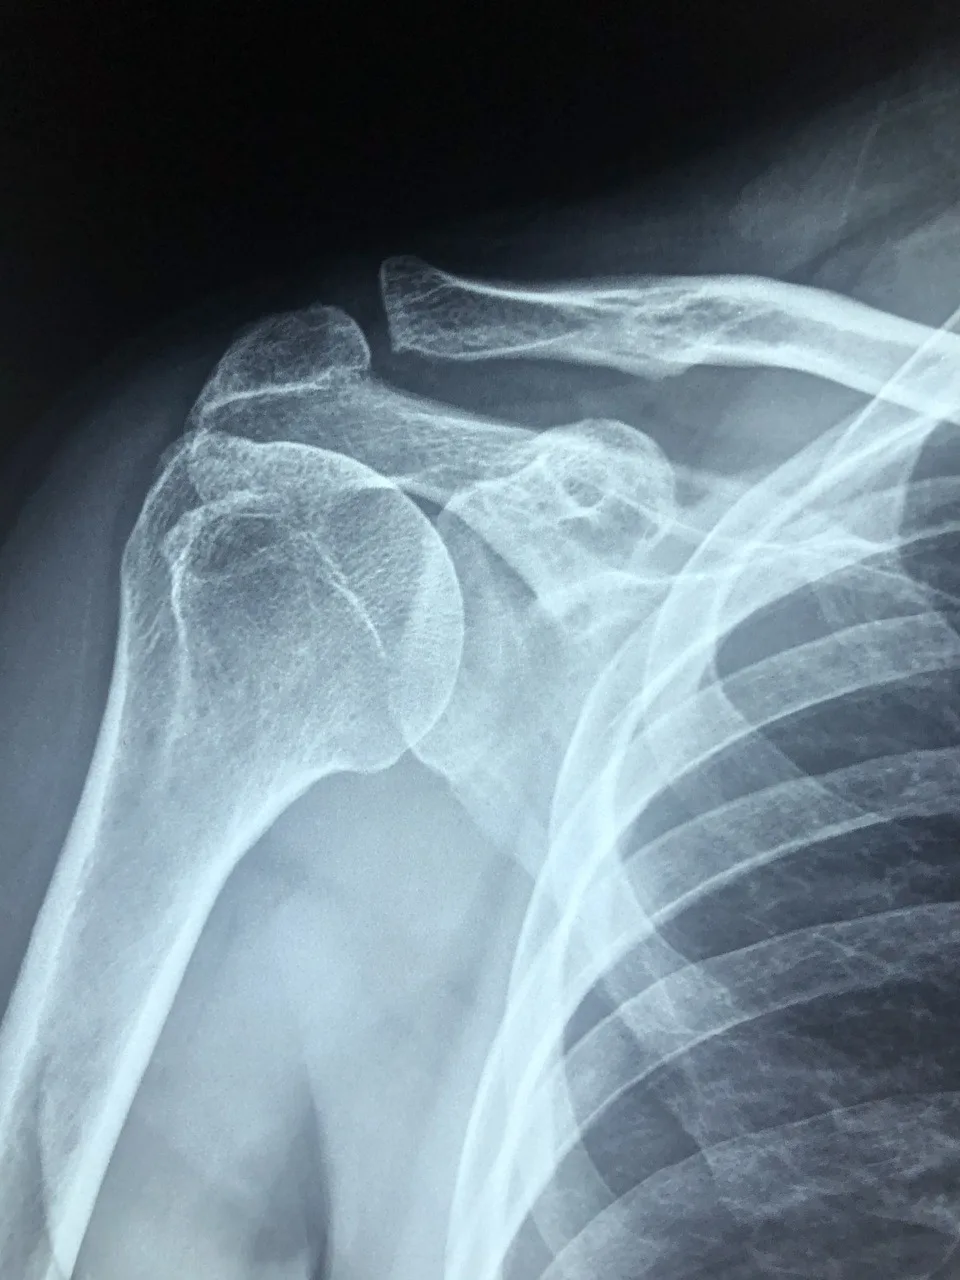

The injection of bone cement is a procedure that is often used to anchor prostheses or artificial joints, but is sometimes used to treat spinal injuries (via vertebroplasty or kyphoplasty) to reduce pain related to vertebral-compression fractures. Unfortunately, at least one company is under investigation for using an unapproved bone cement to treat spinal injuries after multiple patients have died as the cement leaked into their bloodstreams.